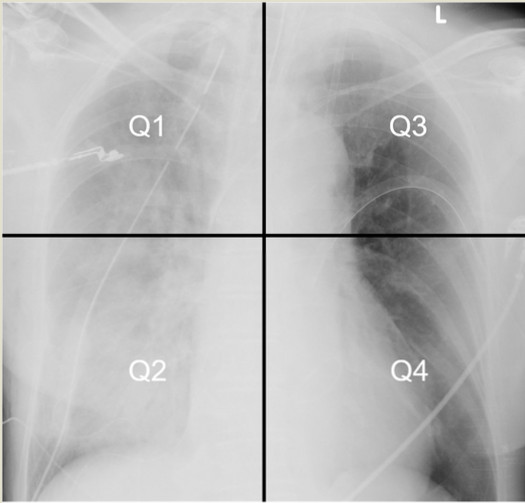

Mostafa等评估肺水肿影像评分(radiographic assessment of lung edema, RALE)诊断UPE的准确性[56]。将胸片分为4个向限,每个向限得分为实变严重程度(0分~4分)×模糊程度(1分~3分),每个向限总分12分,单侧肺总分24分。术后右侧分值大于12分,以及右侧-左侧分差大于13诊断UPE的敏感度和特异度分别为100%和94.4%,88.4%和94.2%(见图 2和表 2)。

| 图 2 肺水肿影像评分 |